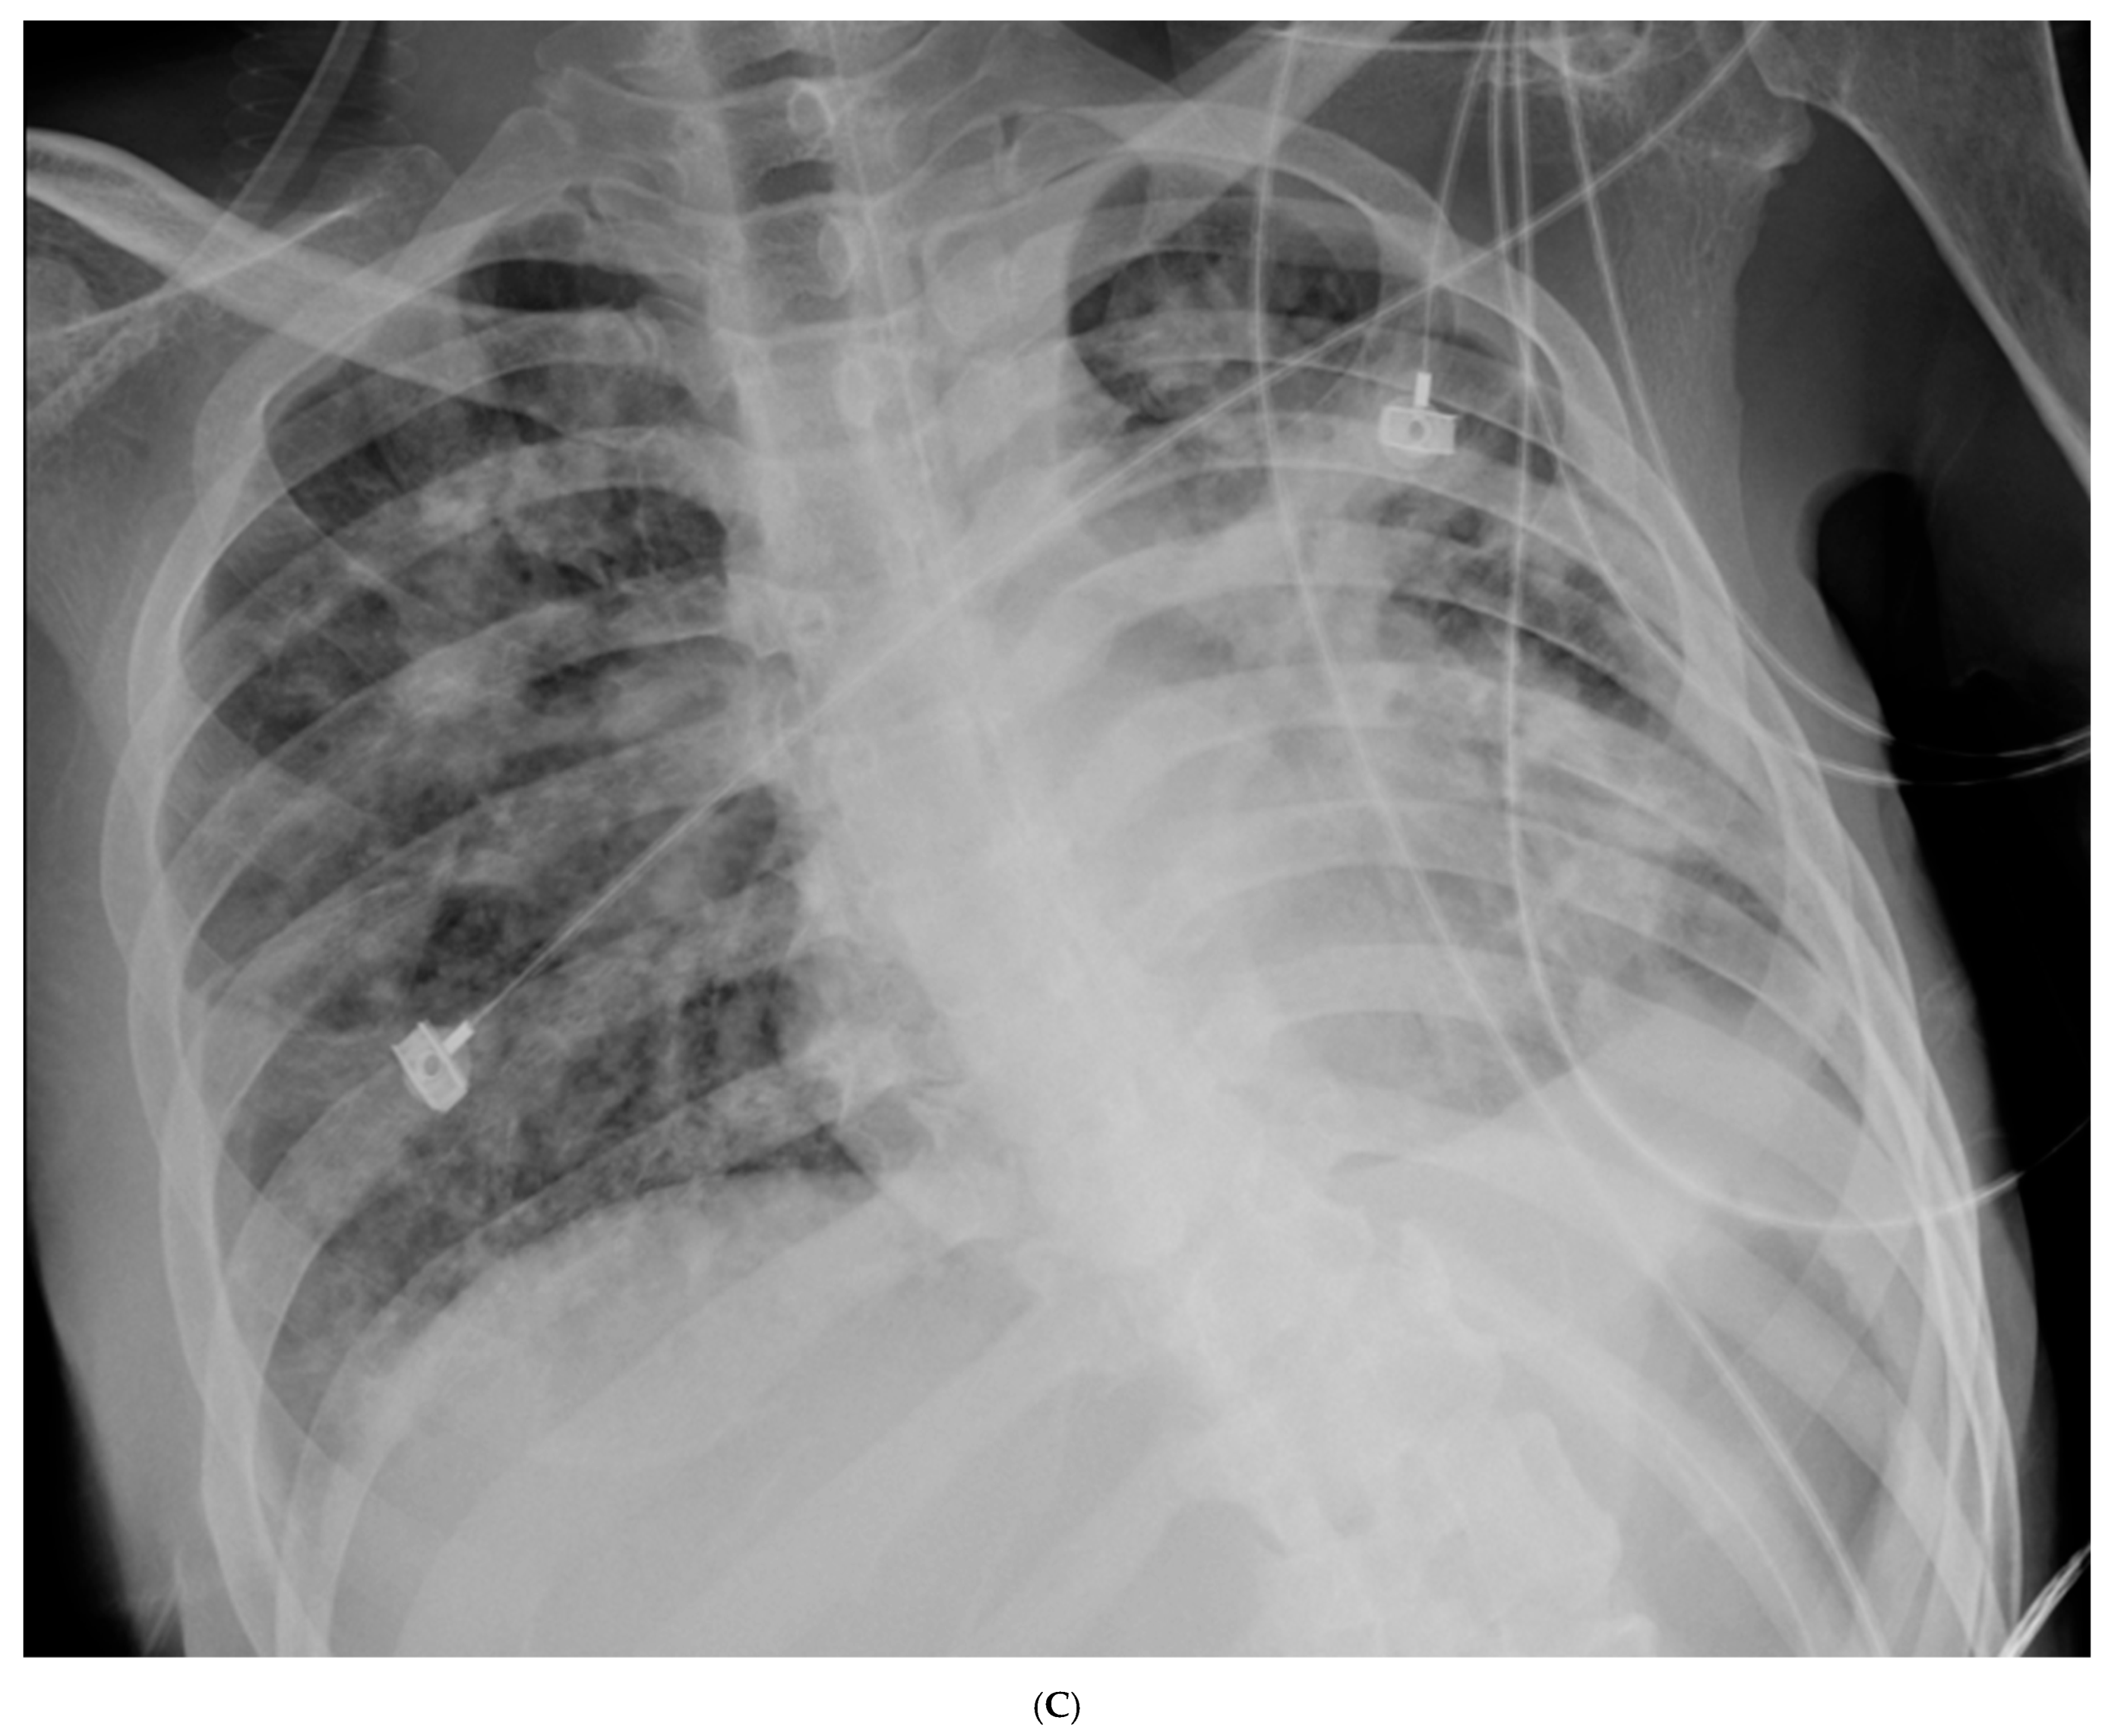

| 45 | Weaning, off steroid/abx | 7.47 | 350 | 0.5 | 9.3 | Off | HREZ | Off | No |

| 54 | Transfer to ward, rehab | 7.45 | 400 (RA) | 0.5 | 11.0 | Off | HREZ | Off | No |

| 45 | Weaning, off abx/steroid | Rehab, spontaneous breathing trial | P/F 350 |

| 54 | Transfer to ward | Anti-TB, rehab | Hb 11.0 |